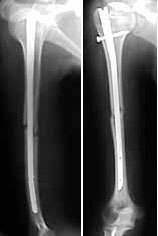

femur

humerus

tibia

The patient came to me two days after injury. Her general condition was not good with Hb 6.7 gm%. After Blood transfusions in the first stage I did standard femoral Interlocking - 10mm nail with two proximal screws. 3 days later I did Tibial and Humeral Interlocking nailing - 8mm and 6mm nail respectively with proximal locking only.

On discharge 10 days later she wass walking independently with Zimmer frame with full knee hip and shoulder movements. Xrays are attached.